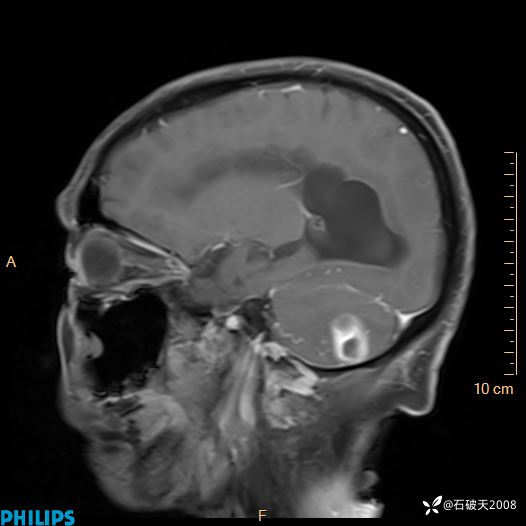

书上说这个肿瘤发生在幕下仅4.09%,你会想到它吗?(病理已公布)

女 86岁 主 诉:乏力1月

现病史:患者1月前活动出现双下肢乏力,无头晕、头痛、恶心、呕吐、肢体活动不利,休息后缓解,间断断发作,症状进行性加重,在家口服药物治疗(具体不详),效差,为进一步诊治,来我院,门诊按“乏力”收住我科,患者自发病以来,神志清,精神稍差,饮食睡眠欠佳,大小便正常,体重未见明显改变。

FLAIR

增强矢状位